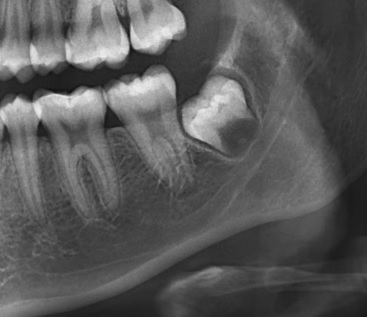

Se presenta la radiografía panorámica (2016) de una paciente femenina de 7 años de edad con un defecto de RIPE en el germen de la pieza 44, de localización distal y profundidad menor a ⅓ de la altura dentinaria (grado I) (figura 2). En la THC adquirida en 2022, con un tamaño de vóxel de 0,15 mm, se observó un defecto hipodenso en forma de fosa, localizado en el esmalte y la dentina (grado I) del tercio medio de la superficie distolingual (figura 3).

Se muestra la radiografía panorámica de una paciente femenina de 15 años de edad, en la que se observa la presencia de un defecto de RIPE de forma triangular bajo el esmalte de la cúspide distal de la pieza 38, de localización central y profundidad dentinal grado I (figura 6). En la THC adquirida, con un tamaño de vóxel de 0,2 mm, se observó un defecto dentinal de forma triangular y de grado I de profundidad, localizado en la cúspide distobucal, además de un defecto hipodenso del esmalte adyacente al defecto (figura 7).

Se tiene la radiografía panorámica de una paciente femenina de 45 años de edad, en la que se observa un defecto de RIPE en la pieza impactada 48, de localización mesial y profundidad dentinal de grado I, y, además, un segundo defecto ubicado en el centro de la corona y de forma alargada, que sería consistente con una fosa vestibular (figura 8). En la THC adquirida, con un tamaño de vóxel de 0,2 mm, se observó que el aparente defecto de RIPE mesial era, en realidad, la fosa mesiobucal y, además, se encontró un defecto de RIPE, grado I, en la cúspide distolingual asociada a un defecto hipodenso del esmalte adyacente al defecto (figuras 9, 10 y 11).